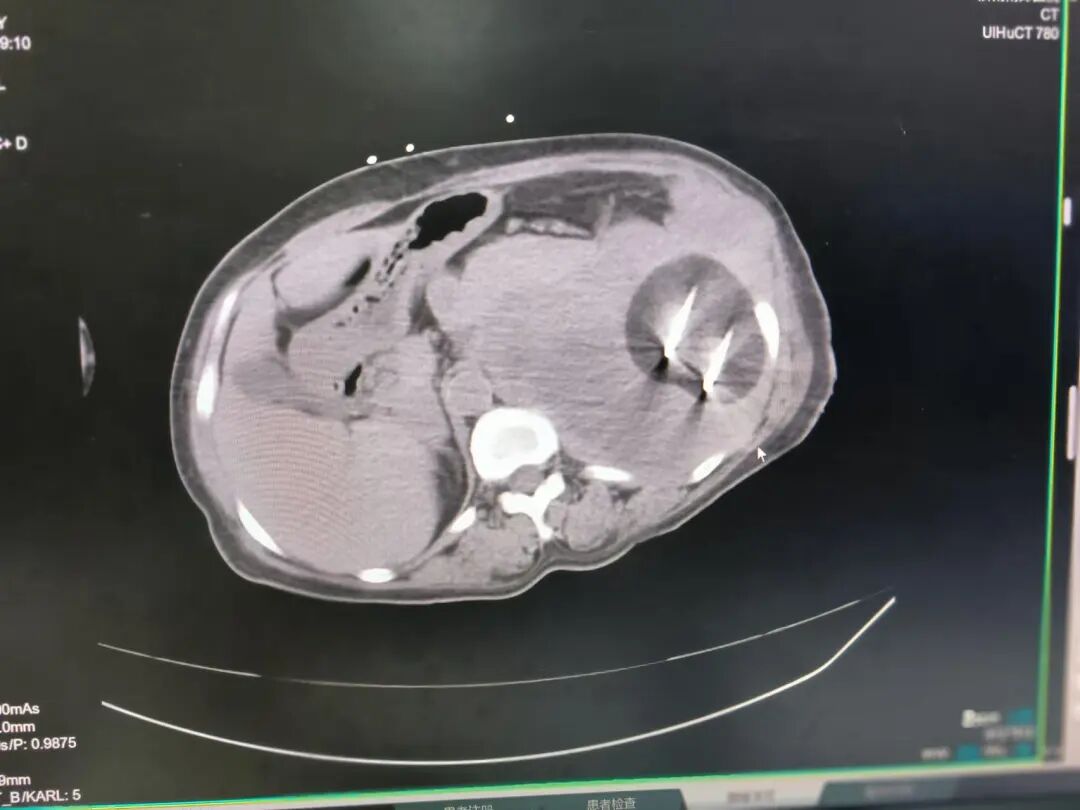

患者因腹部剧痛首次确诊腹腔肿物,手术切除后病理提示“间叶源性肿瘤”。然而,术后复查犹如一记重锤——手术部位再发肿瘤!二次切除后,北京某医院最终明确病理诊断:恶性外周神经鞘瘤(FNCLCC2级),一种具有侵袭性强、易复发特征的罕见软组织肿瘤。更棘手的是,此次肿瘤已压迫胃部,导致患者进食困难、体重骤降,传统手术与放化疗方案均面临巨大风险。

1、精准定位,直捣病灶:在CT引导下,消融针精准穿刺至肿瘤核心,避开周围正常组织;